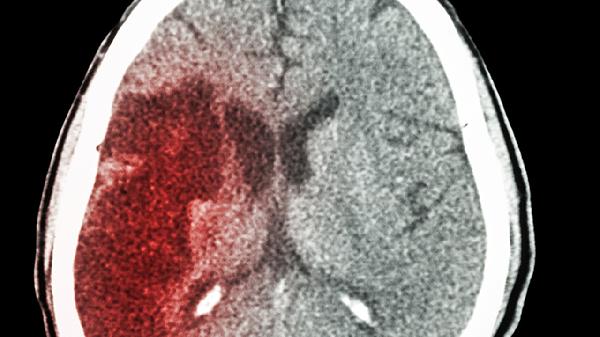

脑部受到冲击后,常见损伤包括脑震荡和颅内出血。脑震荡属于轻度创伤性脑损伤,典型表现为短暂意识丧失、头痛、头晕、恶心呕吐、记忆力减退等,症状多在数日至数周内缓解。颅内出血包括硬膜外血肿、硬膜下血肿和脑内血肿,症状可能逐渐加重,出现持续头痛、呕吐、肢体无力、言语障碍、瞳孔不等大等。严重冲击还可能造成颅骨骨折、脑挫裂伤或弥漫性轴索损伤,后者可能导致长期昏迷或植物状态。

部分情况下,脑部严重冲击的影响可能延迟出现。例如慢性硬膜下血肿可能在受伤后数周才显现症状,表现为进行性加重的头痛、认知功能下降或肢体活动障碍。儿童、老年人及服用抗凝药物者更易出现迟发性症状。极少数情况下,轻微头部外伤可能诱发脑血管异常破裂,如动脉瘤或血管畸形出血,但这种情况较为罕见。

若头部受到严重冲击,建议立即就医评估,尤其出现持续呕吐、意识改变、抽搐、肢体无力等症状时更需紧急处理。医生可能通过头颅CT或核磁共振检查判断损伤类型和程度。恢复期应避免剧烈运动,保证充足休息,遵医嘱进行认知功能训练或康复治疗。日常需注意预防跌倒和撞击,运动时佩戴防护装备,乘车系好安全带,从生活细节降低头部受伤风险。